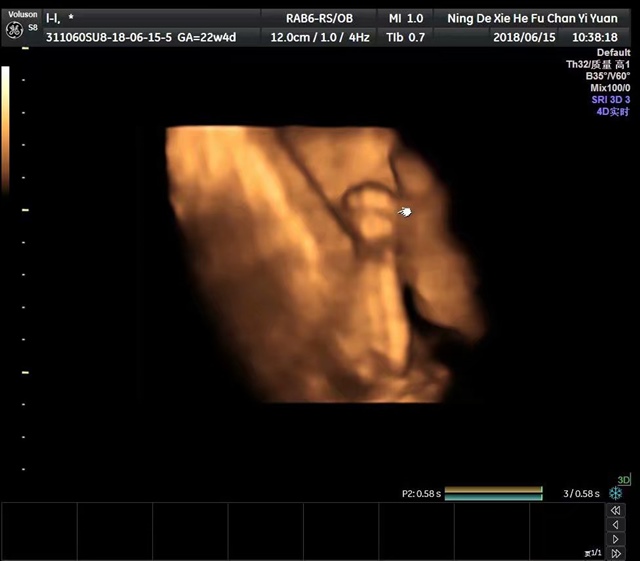

孕23周+0天

是男孩子吗